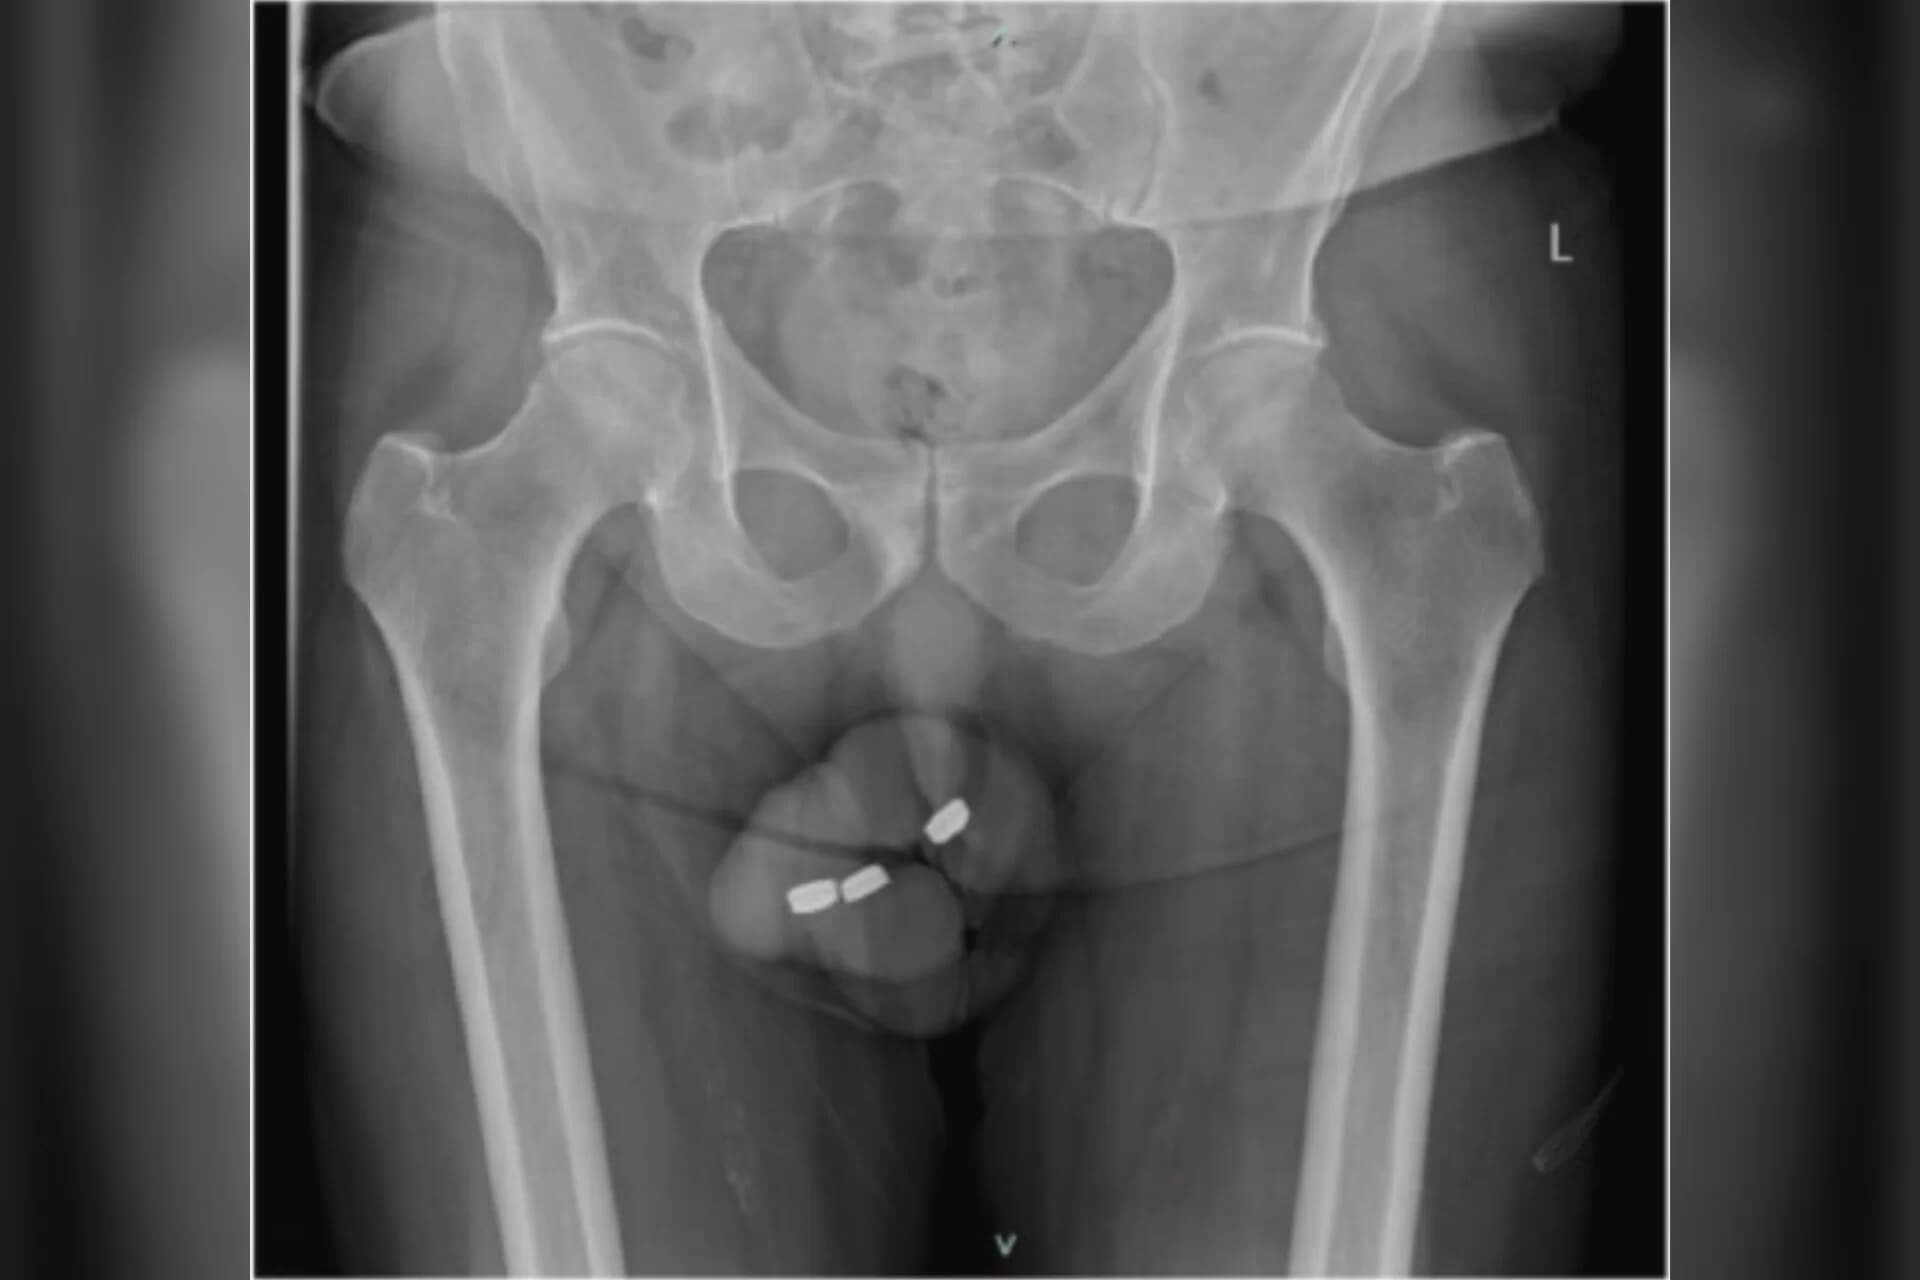

Um idoso procurou uma emergência médica na Austrália com fortes dores no pênis. O paciente de 73 anos, que não foi identificado por razões de privacidade, tinha enfiado três baterias semelhantes às balas Tic-Tac na uretra, canal do pênis por onde passa a urina. O idoso sofria com impotência sexual há três anos e já havia feito inclusive terapias de eletrochoque para recuperar suas ereções.

O homem alegou que tinha o hábito de inserir corpos estranhos na uretra para se masturbar, mas neste caso as baterias entraram mais profundamente no órgão. Desesperado para retirá-las, ele acabou empurrando-as ainda mais.

Ao chegar ao hospital, o paciente não conseguia urinar e estava com o órgão todo inchado. Além disso, a bateria enfiada por último havia se danificado lá dentro e os médicos temiam o vazamento de elementos corrosivos no corpo do paciente.

“Este é o primeiro caso de inserção de baterias deste tipo na uretra. Sabemos de casos da inserção de uma grande variedade de corpos estranhos como fios, ossos, talheres, alfinetes, termômetros, cotonetes e vermes, mas bateira foi a primeira vez e os traumas de seus produtos químicos são extremamente prejudiciais”, escreveram os médicos em um artigo sobre o caso no na Urology Case Reports, publicado no último dia 10.